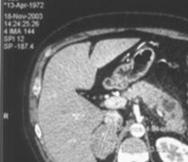

На рис.8 представлены изображения снятые при неудачном (слева) и правильном

(справа) выборе параметров съемки.

Рисунок 8

-Изображения, полученные при разных значениях параметра съемки.